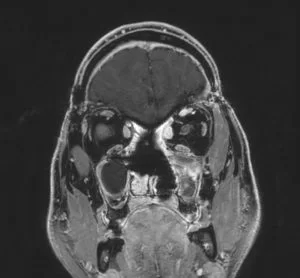

Ακουστικό Νευρίνωμα αριστερά

Ασθενής άνδρας, 52 ετών με κώφωση αριστερά και ιλιγγική συνδρομή. Η μαγνητική τομογραφία εγκεφάλου ανέδειξε χωροκατακτητική εξεργασία στην αριστερή γεφυροπαρεγκεφαλιδική